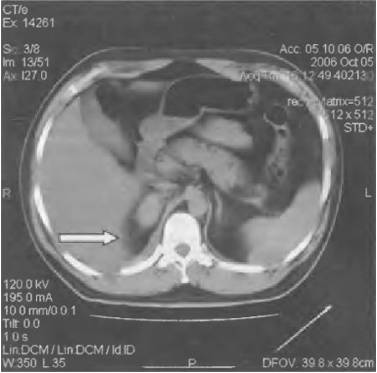

Гидронефроз

Прогрессирующее расширение собирательных полостей почек, которое приводит к их дисфункции.

Характер и локализация боли

Гидронефроз характеризуется ноющими болями в области живота, боков, поясницы и крестца.

При поражении правой почки болезненность ощущается преимущественно справа.

Диагностика и лечение

Диагностировать заболевание можно при помощи анализа крови, УЗИ почек, экскреторной урографии, КТ и МРТ.